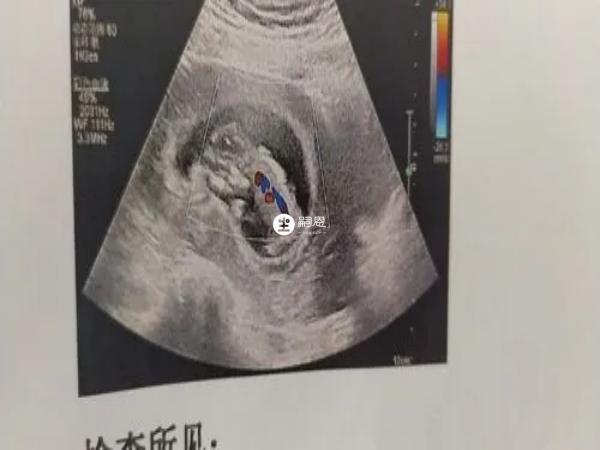

nt資料看男女的方法在國外比較流行,判斷是生男孩還是生女孩,主要通過尾椎與身體所成角度進行判斷,懷的是男孩的話特徵點與身體呈現45度角,懷女胎的話,通常尾椎與軀幹平行,中間幾乎為零度角,這也是通過NT看胎兒性別的一個方法。

有寶媽分享已驗證生女孩的nt影象,其實nt看男女是非常準的一種方法,不過要想準確判斷,也需要具有專業知識才行,普通人一般很難分辨,或者醫院給出的nt單子可能並不是全景圖,會對胎兒性別特徵進行隱藏。另外,胎兒寶寶不同的體位,拍攝的角度,都會對判斷胎兒性別造成影響,需要多熟悉方法和技巧。

5、已生女兒nt檢查圖片